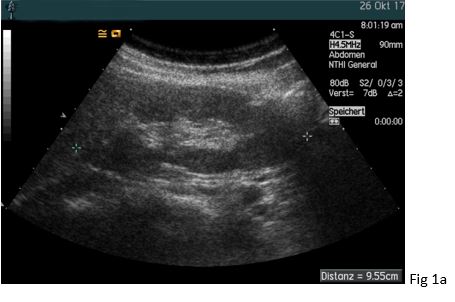

A 37 yo female patient suffered from chronic headaches. She was examined by a neurologist who diagnosed fibromyalgia. Her family practioner also diagnosed severe arterial hypertension (so-called “non dipper”) and excluded hyperaldosteronism, hyperthyroidism and sleep apnoea as secondary causes. Anti-hypertensive medication was initiated with amlodipine and ramipril. Although she is a smoker (> 20 py) there were no ultrasonic features of atherosclerosis. However, her estimated glomerular filtration rate was reduced (~68 ml/min/1,73m²). Auscultation also revealed a high frequent upper quadrant noise on the right side. The general practioners initial ultrasound showed a significant difference in the size and resistive index (RI) between the right and left kidney. For that reason, the patient was sent to our specialist hypertension center where the diagnosis of renal artery stenosis caused by fibromuscular dysplasia was confirmed.

The peak systolic velocity (PSV) in the renal artery is physiologically below < 1.5 m/s and typically around 1 m/s. In contrast, values > 1.8 m/s are indicative of significant stenosis. The normal RI values within the kidney are in the range of 0.55 - 0.65 and typically below 0.7. The normal values are increasing with age (up to 20 %) (1, 5, 6).